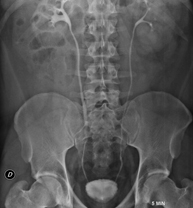

- RX Abdomen

Técnica mediante la cual, utilizando rayos X, se obtienen imágenes del abdomen (estómago, intestino delgado, intestino grueso, hígado, riñones, vejiga, pelvis ósea, etc.) para su estudio. - RX Columna lumbar